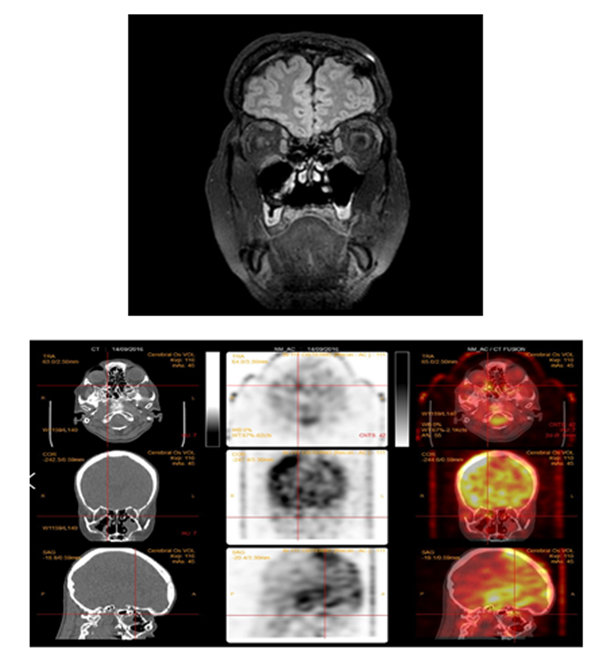

Postoperative imaging (MRI and CT scans) confirmed the persistence of CSF leak at both the cribriform plate and thoracolumbar levels (Figure 3). Isotope cisternography likewise showed residual tracer accumulation at these sites. Connective tissue disorders were ruled out.

Figure 3A: Postoperative MRI shows the encephalocele and the periosteal graft sealing the CSF leak at the right paramedian cribriform plate. B: Isotopic cisternography with CT fusion demonstrates persistent CSF leakage at the cribriform plate and at the spinal cysts.